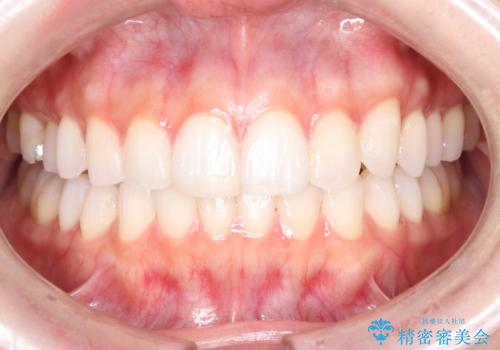

欠けやすい大きなプラスチック充填から、耐久性の高いセラミッククラウンへ

担当医 河口智英